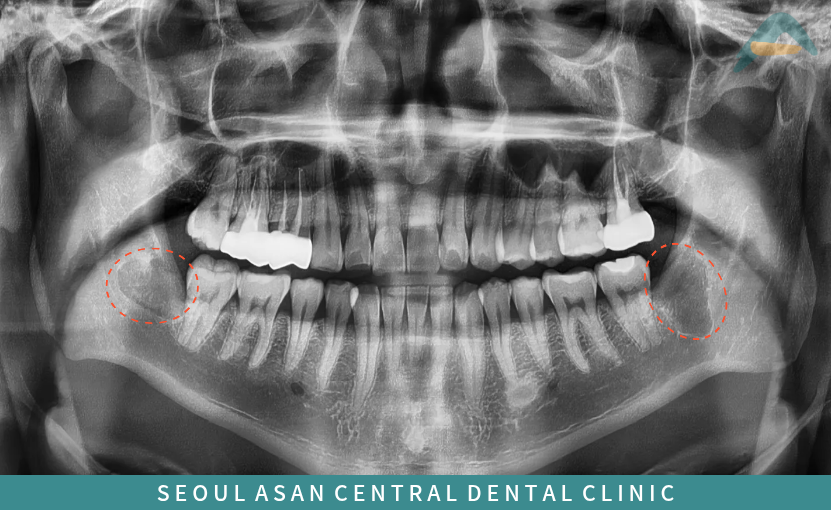

해당 파노라마 사진에서

보이는 것과 같이

아래턱 양측 사랑니가

모두 치아의 일부만 잇몸뼈 위로

맹출 되어 있는

반매복 상태의 형태를 보이고 있는데요.

수정구치과에서는 발치를 진행하기 전

파노라마 사진과 3D CT 촬영을 통해

치아 뿌리 끝부분과

아래턱 하방으로 지나가는

하치조 신경과의 거리를

면밀하게 파악하는 과정을

거치는게 필요한데요.